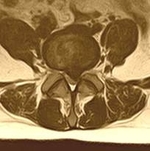

Такой уникальный комплекс хирургически-диагностического оборудования позволяет быстро и эффективно проводить операции на позвоночнике пациентам с такими болезнями, как межпозвоночная грыжа диска, стеноз позвоночного канала, перелом позвоночника и другими заболеваниями, при этом сроки госпитализации для хирургического лечения составляют от 3х до 7ми дней.